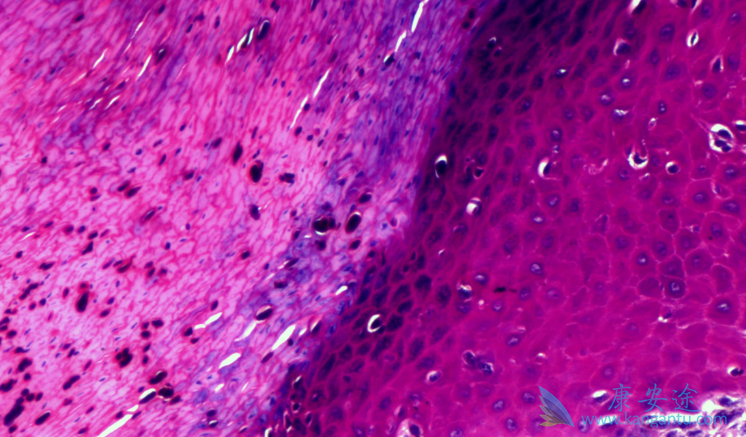

什么是恶性黑色素瘤?恶性黑色素瘤是皮肤癌,是恶性程度高、发病率增长迅速的肿瘤之一。患者往往不能及时发现症状,等到就诊时,多数已经晚期。我国此种病的发病率逐年增长,估计每年新发病例约2万例。此种瘤大多发生于肢端脚底、手掌等部位,而容易受到摩擦的部位更可能发生恶变。如果发现有“疑似”情况,可以到医院门诊进行手术。

如何进行手术与检查?一旦发现恶性黑色素瘤的影子,外科手术治疗方式是首选。但不是说想切多少切多少,外科治疗是有明确规范的,评判标准是根据恶性黑色素瘤的厚度:当厚度≤1.0mm,临床切1cm;厚度为1.01-2.0mm,临床切1-2cm;厚度>2.0mm,临床切2cm,考虑颜面部等特殊位置,可适当缩小切缘范围,但不应少于1cm。需注意的是因缺乏肿瘤厚度,切缘选择根据皮损范围扩大1cm-2cm全层切除。